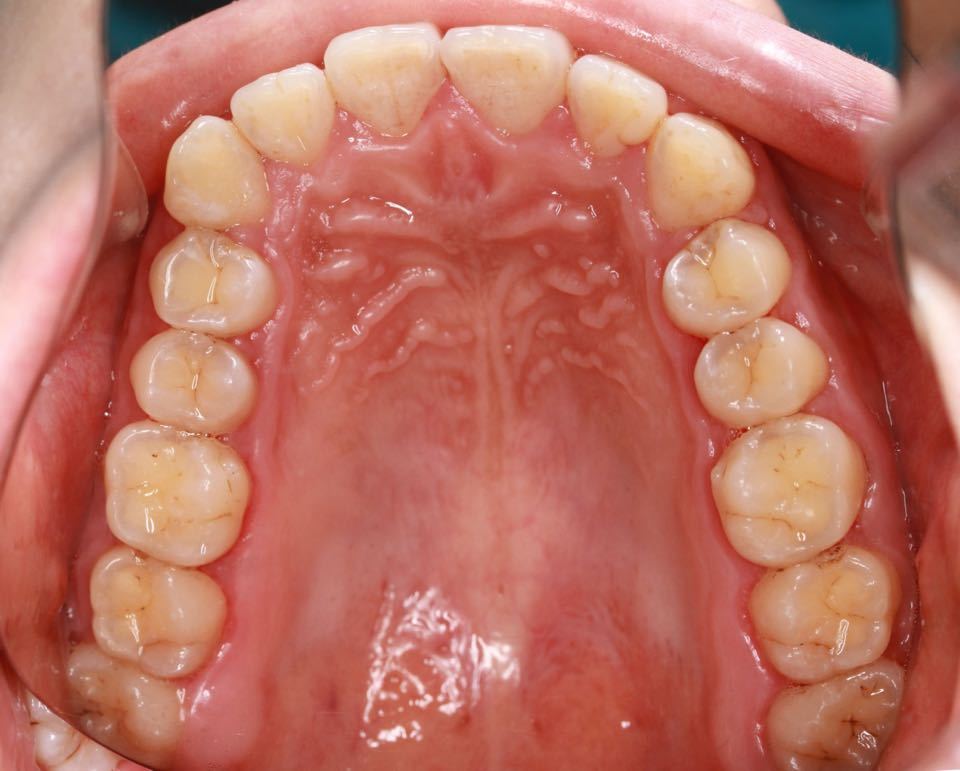

矫正后口内照:

治疗改善:关闭散隙,调整中线。

目前阶段:全口牙齿排列整齐,中线居中。前牙覆合覆盖正常,尖磨牙关系达I类咬合关系。总疗程约18个月。